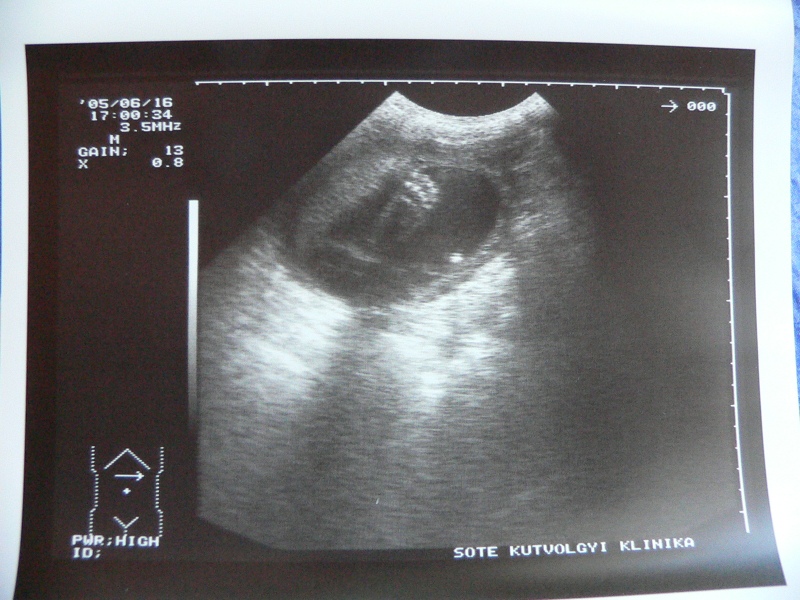

| 12. heti ultrahang. 6,5 cm.

láb, test, fej, kezek láthatóak. |